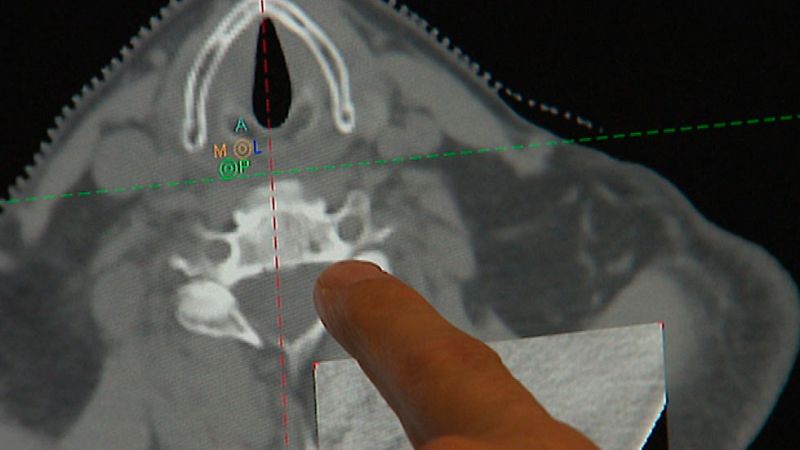

Descubren el posible talón de Aquiles del VIH: la membrana que lo recubre

- Alterar su estructura podría ser clave para bloquear el contagio

- El hallazgo abre la puerta al diseño de nuevas armas contra el virus

- Lo ha averiguado un estudio internacional en el que participa la Complutense